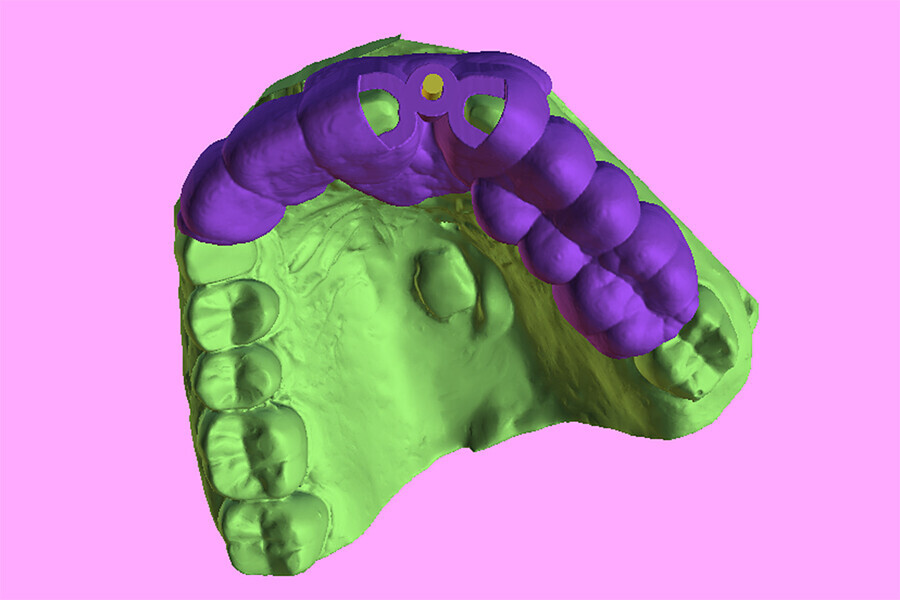

Fig. 6a: Two 3D-printed templates designed on the digitised model (green): one for the initial drill to section the tooth at the root apex (a) and the second for using sequential guided drills to drill through the root itself (b).

Fig. 6b: Two 3D-printed templates designed on the digitised model (green): one for the initial drill to section the tooth at the root apex (a) and the second for using sequential guided drills to drill through the root itself (b).

Fig. 15a: The base template was designed to seat firmly on the adjacent teeth, incorporating buccal and lingual hexagonal offsets to engage the different drill

guide inserts.

Fig. 15b: Separate inserts were fabricated for the initial drill guide to reach the root apex to accommodate sectioning, followed by a second guide for final osteotomy drilling and implant placement.

Fig. 15c: Separate inserts were fabricated for the initial drill guide to reach the root apex to accommodate sectioning, followed by a second guide for final osteotomy drilling and implant placement.